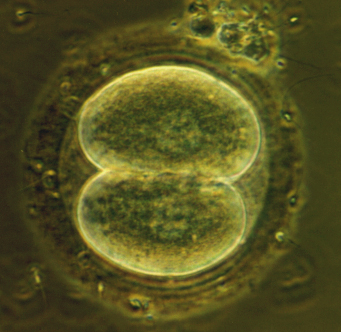

2 cells stage embryo

4 cells stage embryo